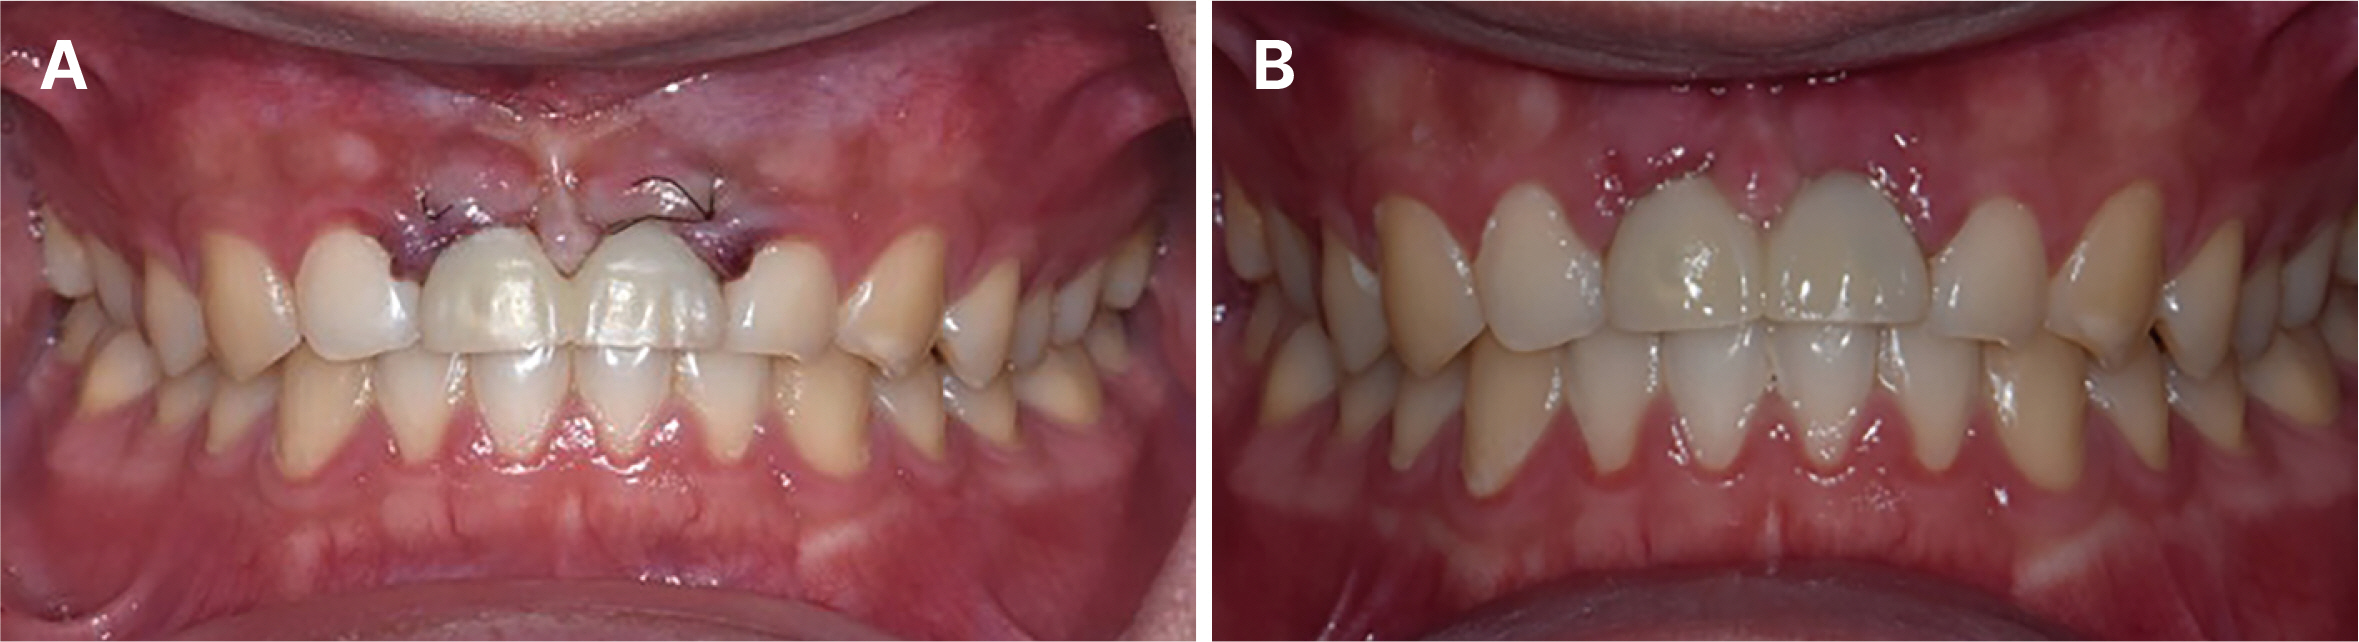

Aesthetic prosthetic restoration through immediate implant placement and provisional restoration in the maxillary anterior region using a digital guide

- Immediate implant placement and immediate loading in the anterior maxilla is an effective approach to rapidly address aesthetic demands. To achieve successful outcomes, bone quality, soft tissue condition, and accurate implant positioning are essential factors. For optimal results, procedures such as bone augmentation, precise implant placement, and, when necessary, soft tissue grafting should be considered. Furthermore, provisional restoration play a crucial role in achieving the desired appearance of prosthetic restorations and improving the aesthetics of the soft tissue. By performing soft tissue molding through provisional restoration, an ideal emergence profile can be established, which can be subsequently transferred to the final prosthesis, leading to a functional and aesthetically pleasing restoration. This approach aims to optimize the aesthetic outcomes in the anterior region while preserving the natural contours of the peri-implant soft tissue. In this case, a patient requiring extraction of maxillary anterior tooth underwent immediate implantation and alveolar bone grafting using a guide fabricated in advance from CT data. The patient received a provisional restoration on the same day. Subsequent steps included transitioning from the provisional prosthesis to the definitive prosthesis, ultimately achieving an aesthetically pleasing and functional implant restoration. We report this case to highlight the successful approach to maxillary anterior implant rehabilitation.